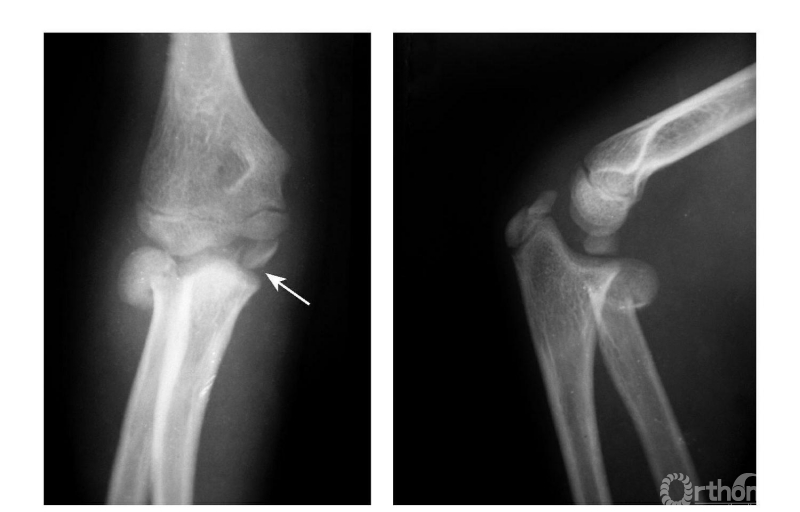

例2:内上髁撕脱骨折,骨块移至尺肱关节间(成人)(图7)。

图7

例3:肱骨内上髁Ⅲ度骨折并桡骨颈骨折(歪戴帽)(图8)。

图8